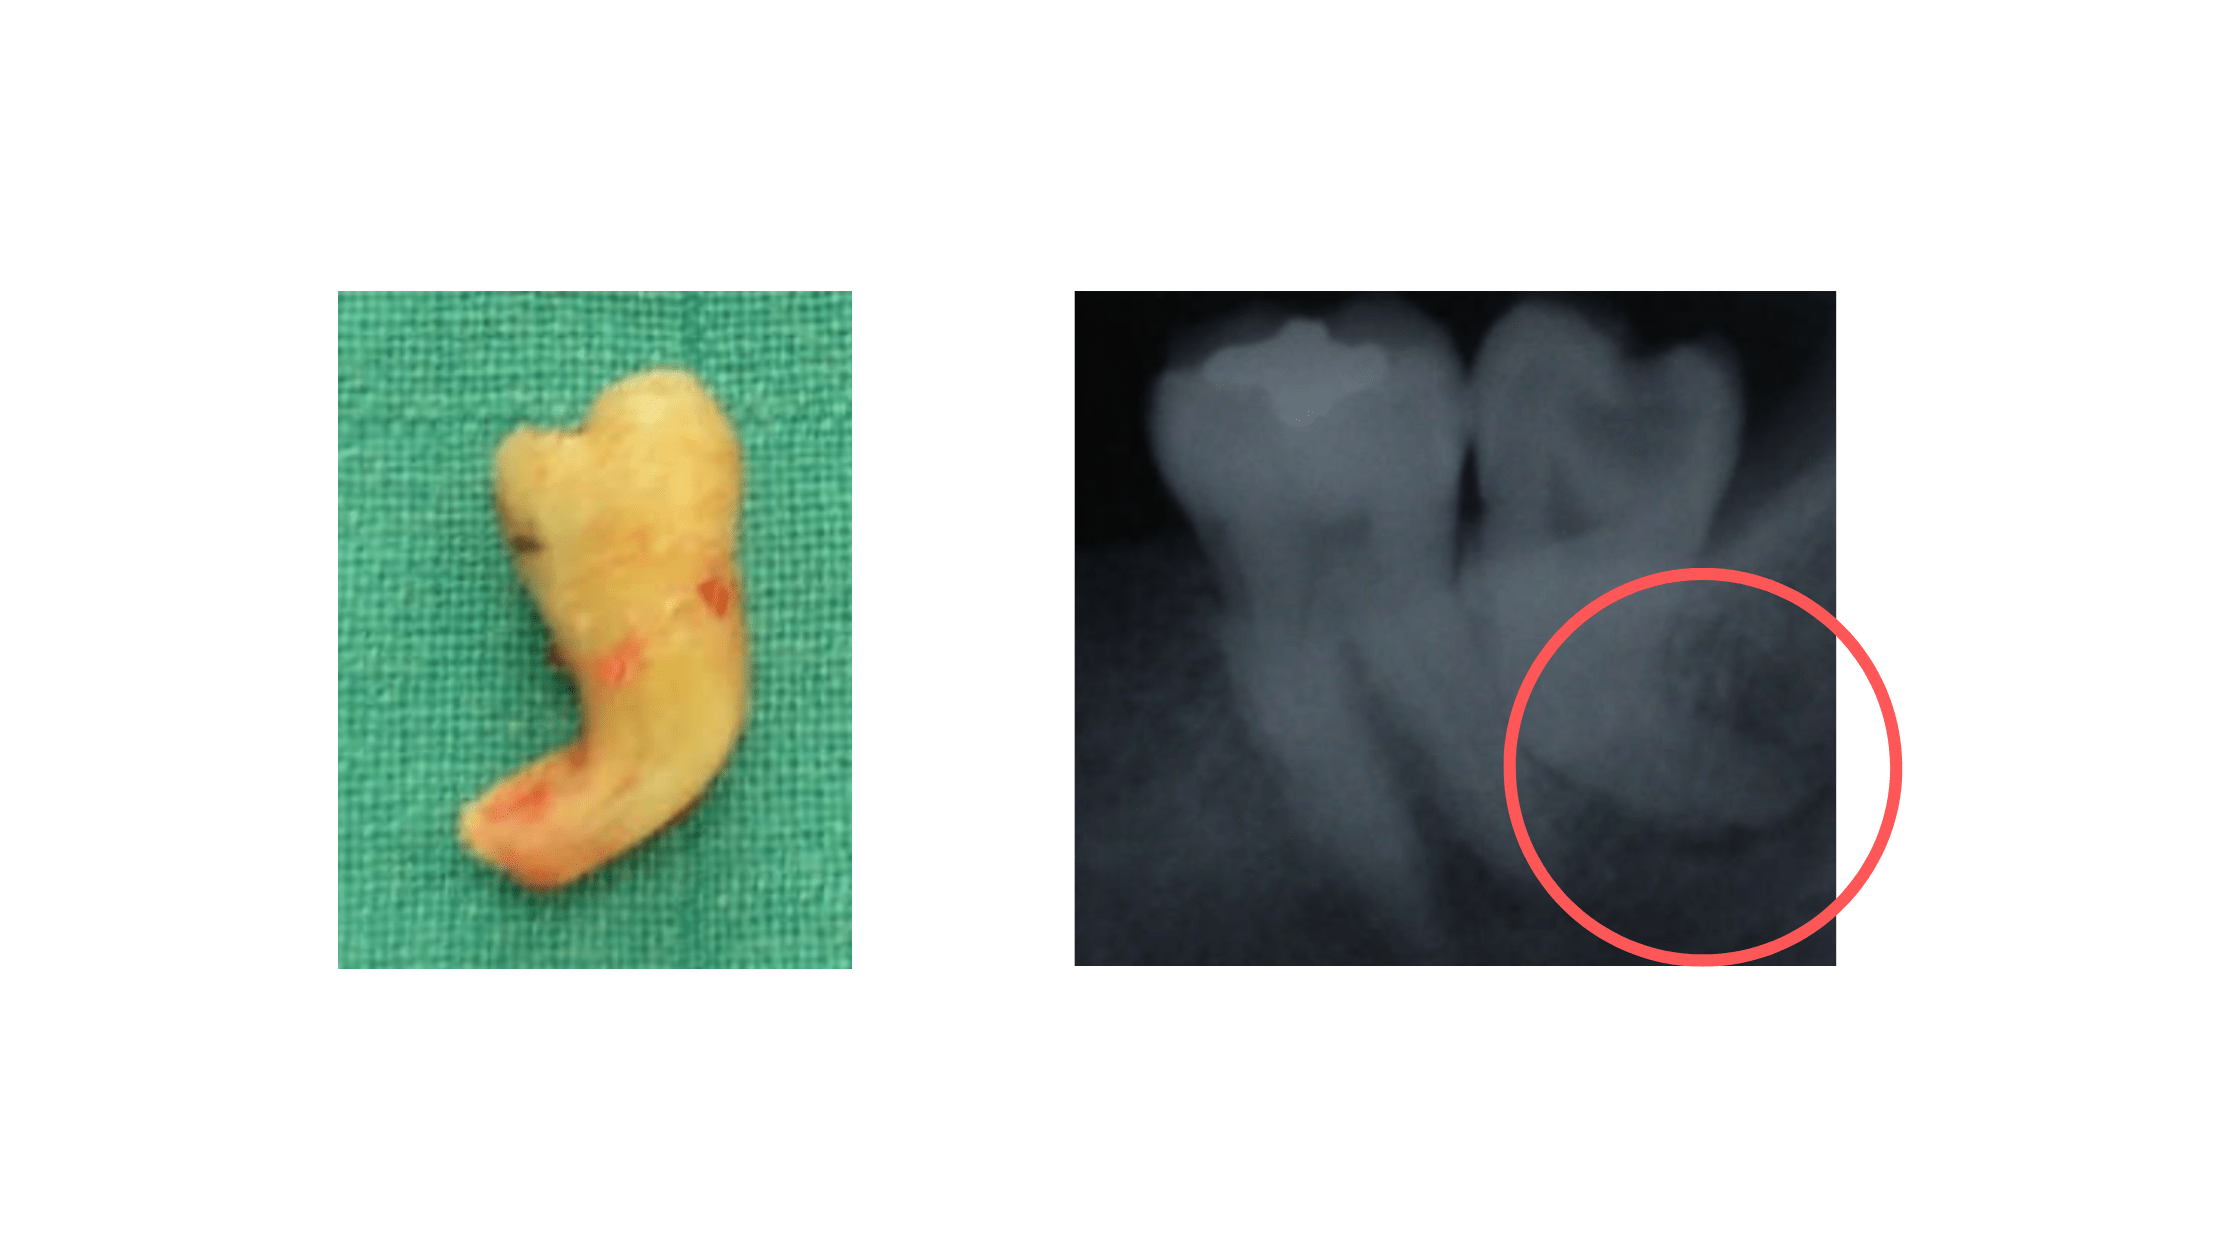

Wisdom Teeth With Curved Roots Removal/Treatment Torrance Oral Curved Root Tooth Extraction Pain Extracting a curved root can be more difficult and potentially more painful than a regular tooth. Usually tooth removal is straightforward and takes a few minutes. Root tip fracture can occur during the extraction of teeth. In these cases, pain management is very important. Pain, swelling, soreness and intermittent bleeding from the site of the extraction. If you’re scheduled to. Curved Root Tooth Extraction Pain.

Erupted Wisdom Teeth with Curved Roots Extraction Video YouTube Curved Root Tooth Extraction Pain The pain experienced after treatment depends on the difficulty of the surgery and each individual. If you’re scheduled to have a tooth extraction, you might be. What is the pain in the extraction of a curved root? Root tip fracture can occur during the extraction of teeth. What is involved in removing a tooth? Pain, swelling, soreness and intermittent bleeding. Curved Root Tooth Extraction Pain.

38 Badly Decayed With Curved Roots YouTube Curved Root Tooth Extraction Pain Extracting a curved root can be more difficult and potentially more painful than a regular tooth. Pain, swelling, soreness and intermittent bleeding from the site of the extraction. In some cases, root tip extraction is necessary when a simple extraction leaves behind the very end of the tooth’s roots. Usually tooth removal is straightforward and takes a few minutes. What. Curved Root Tooth Extraction Pain.